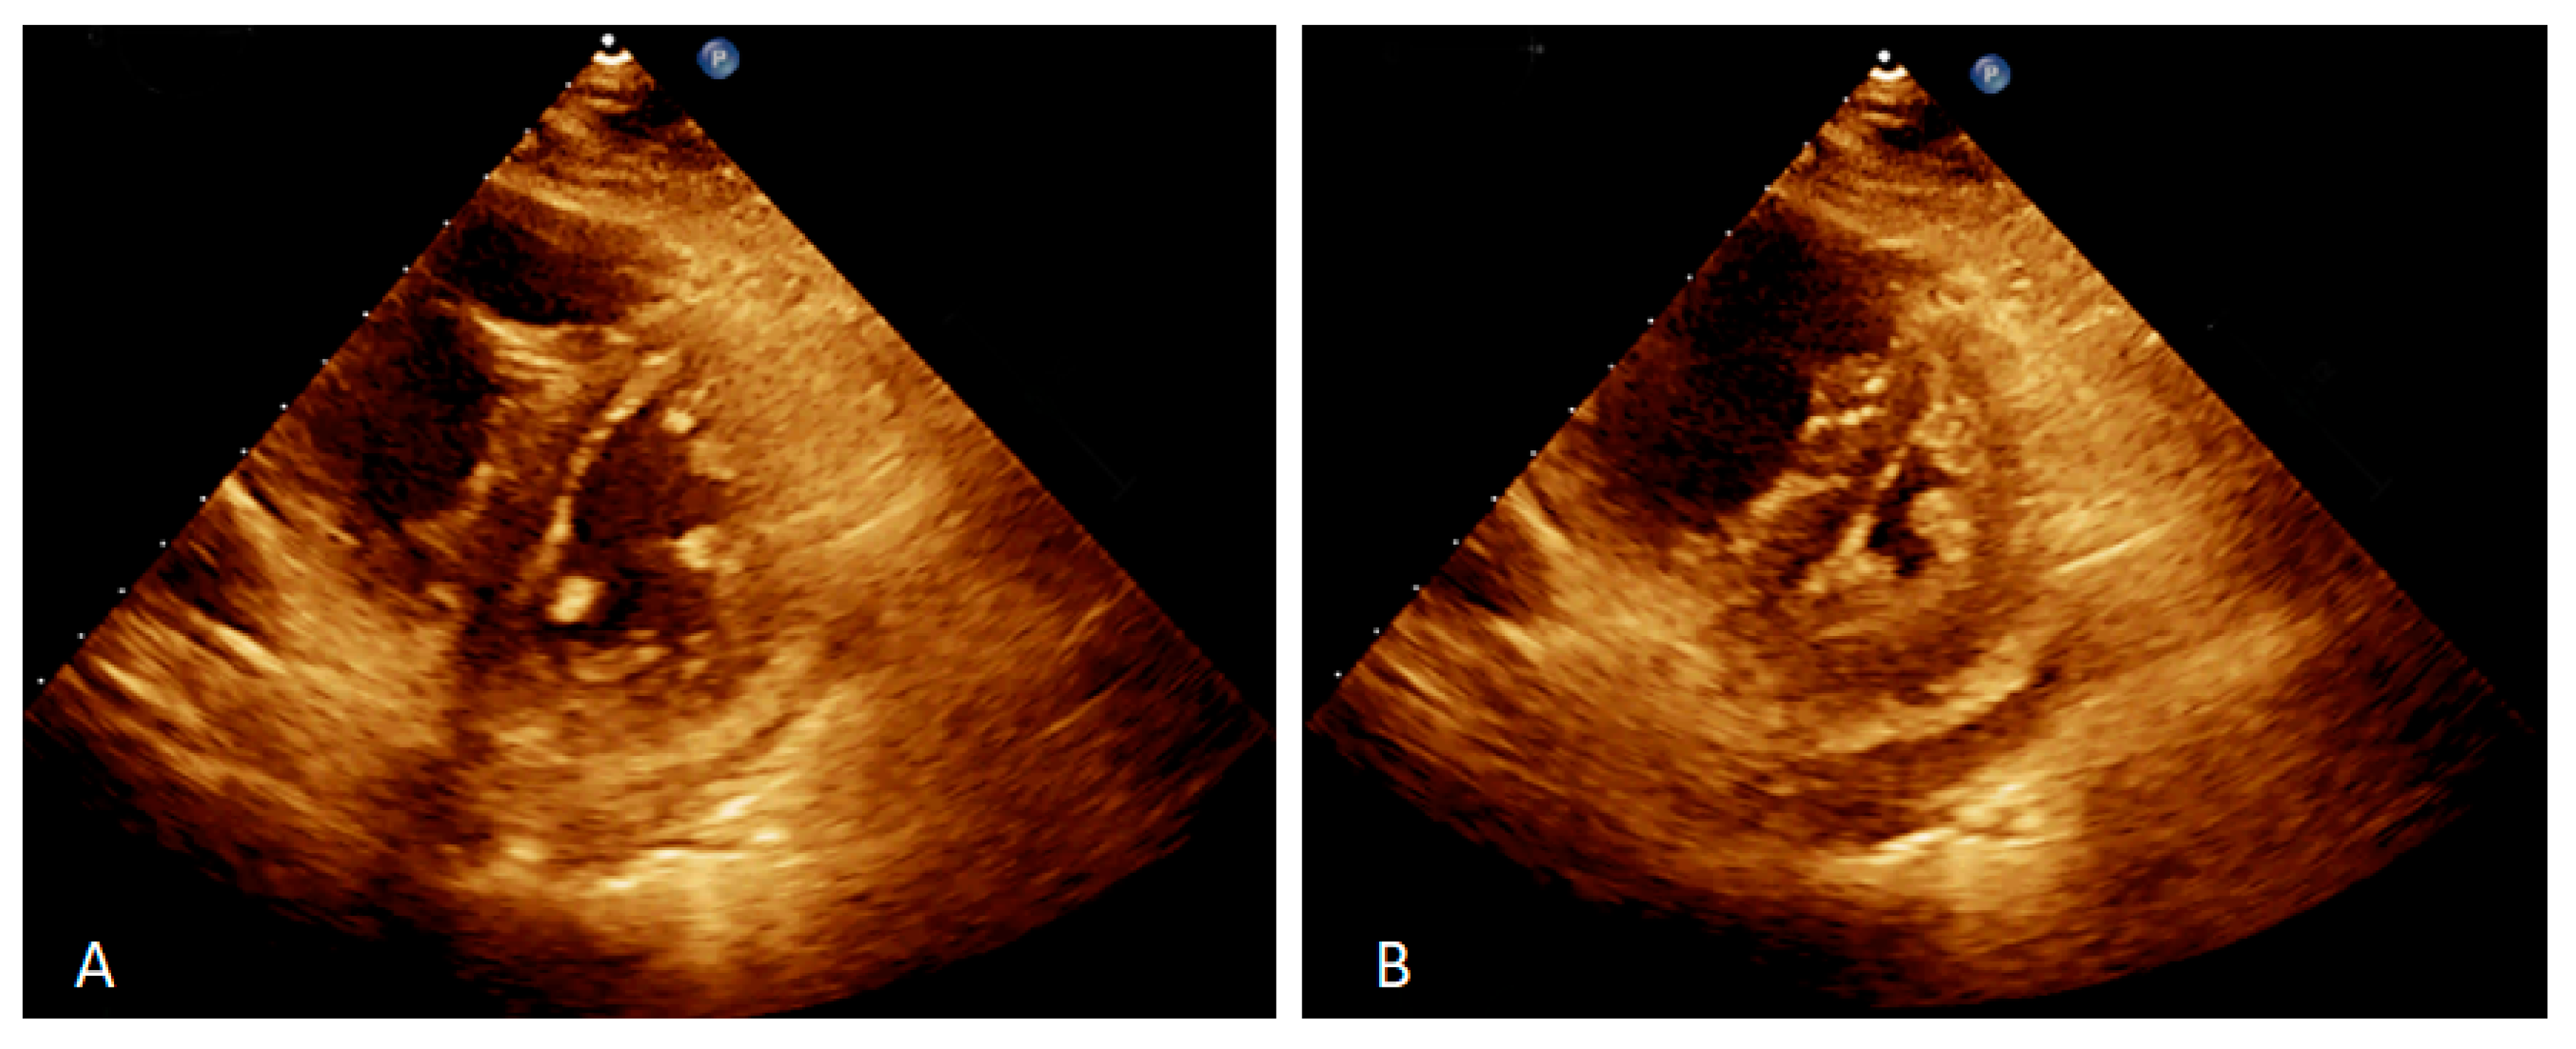

2. Case Presentation